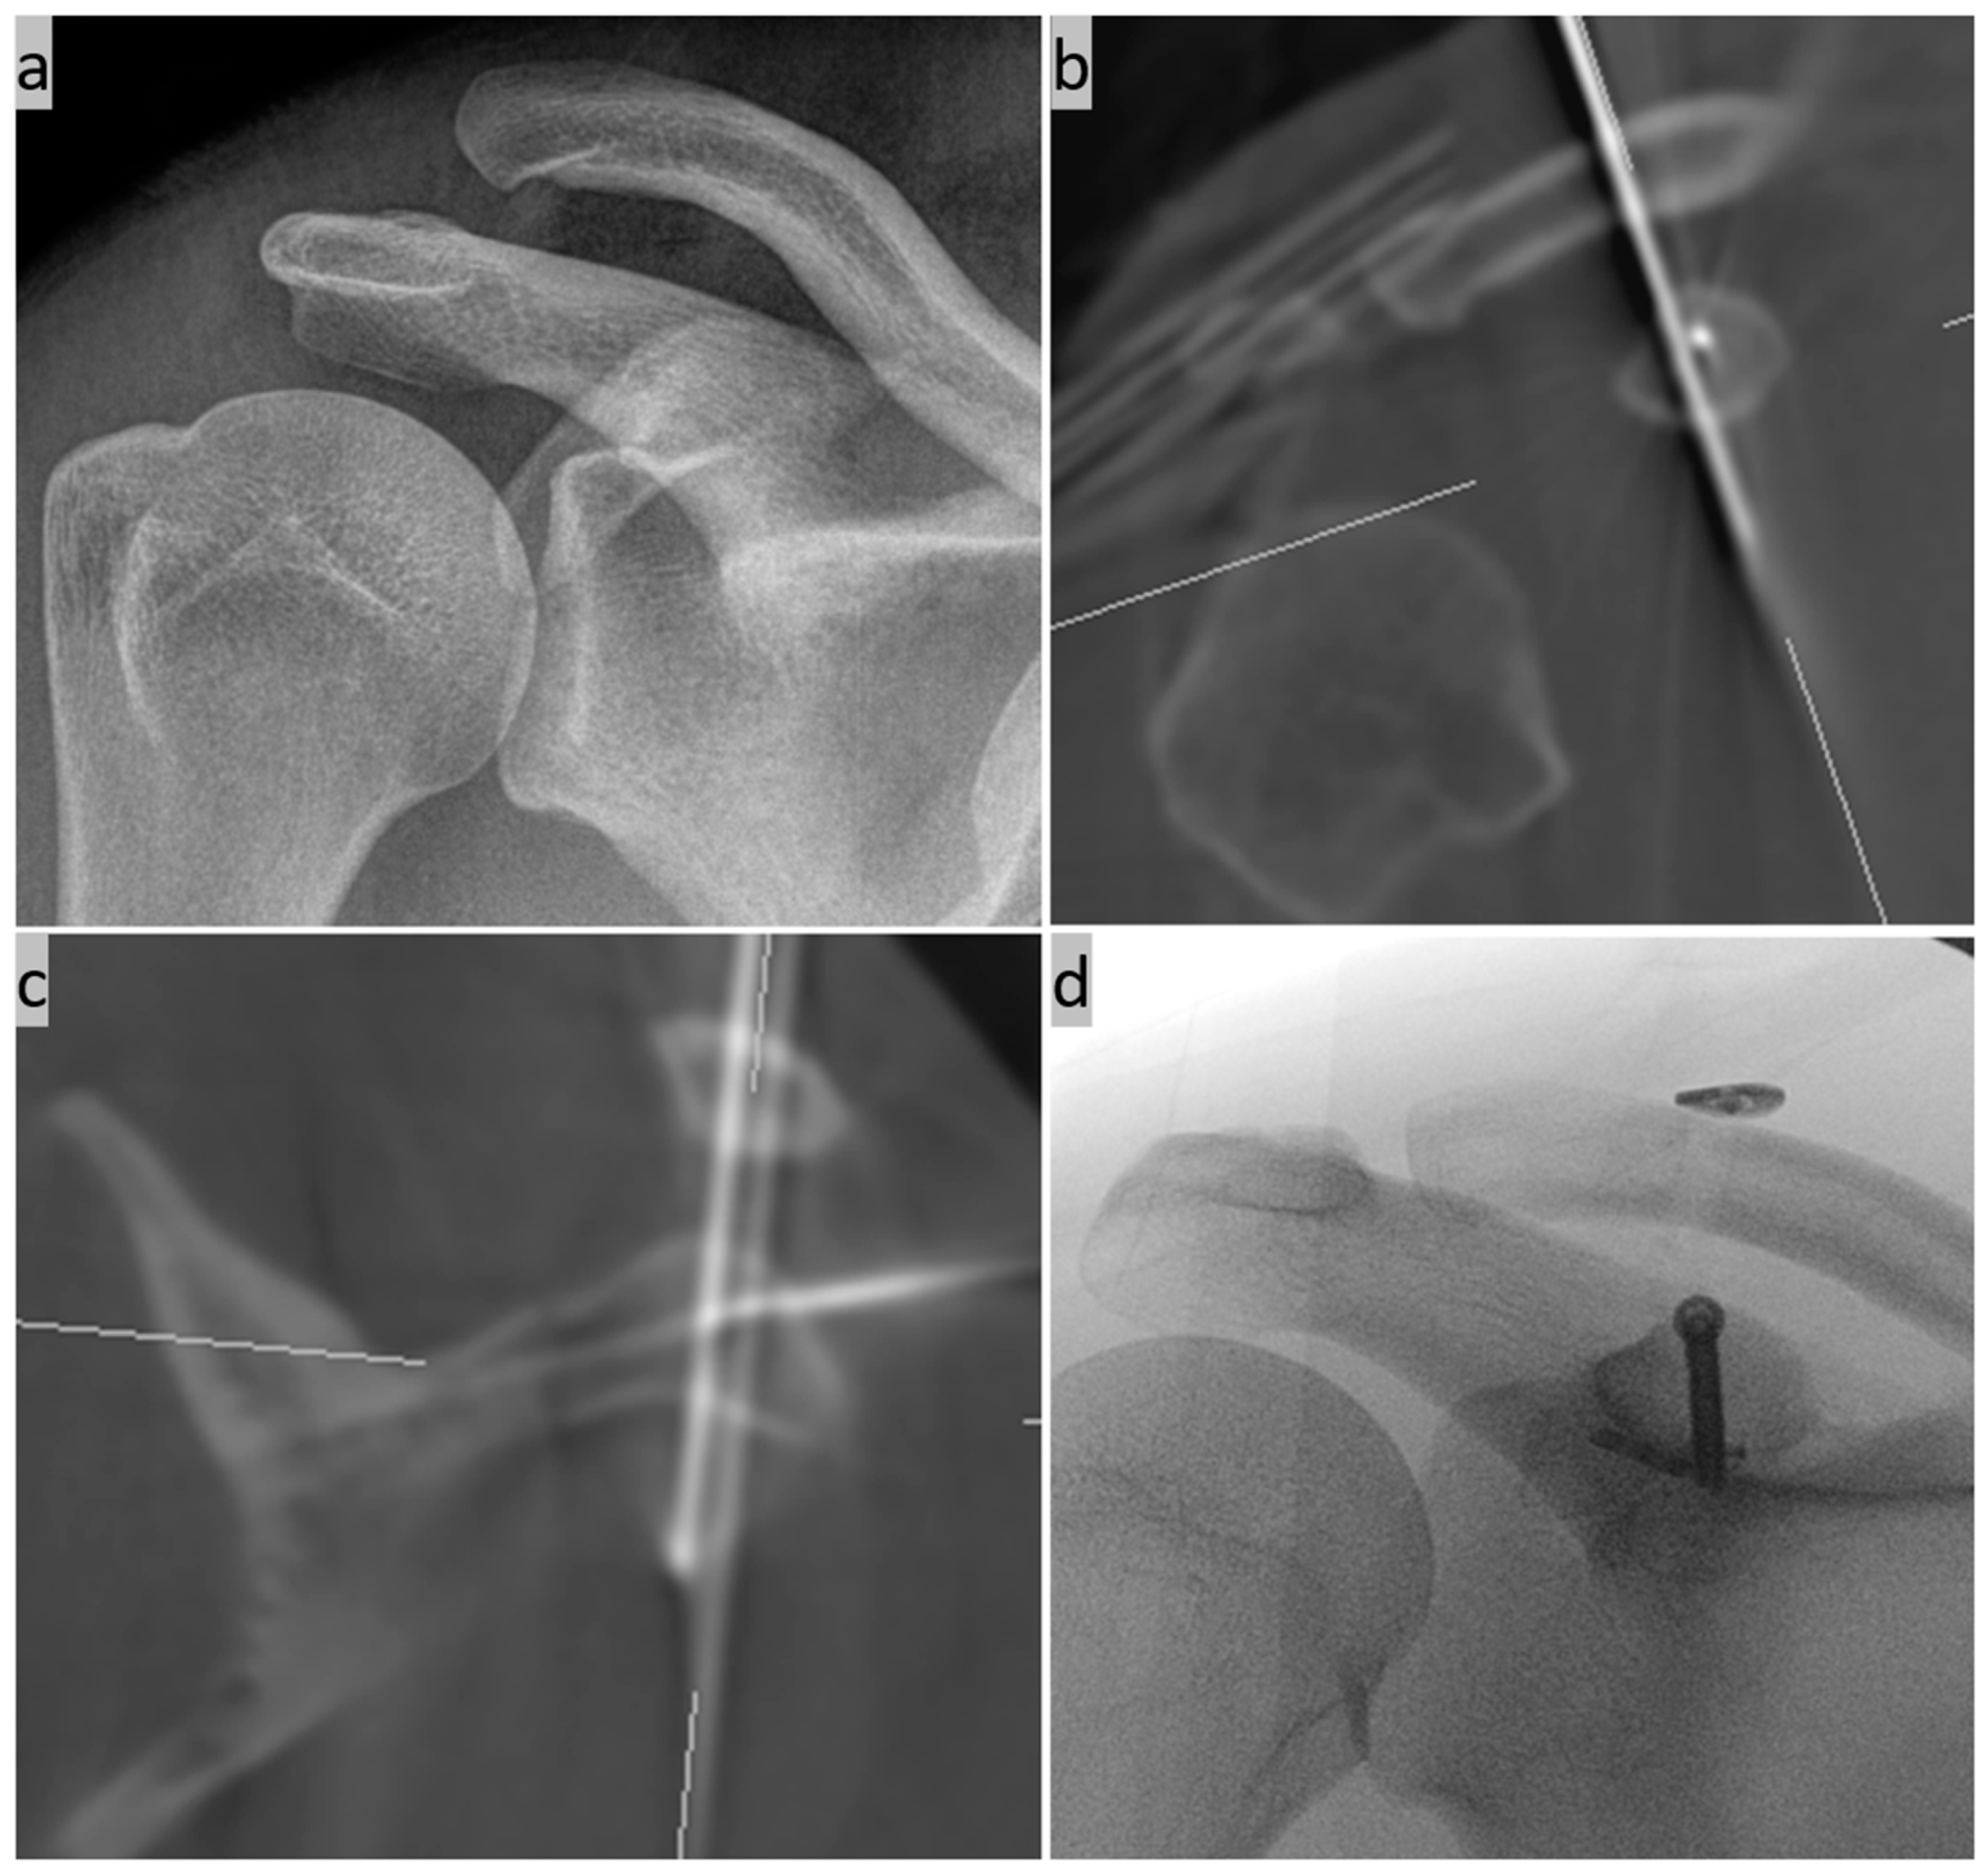

2. Surgical Technique

- Böhringer, A.; Gebhard, F.; Dehner, C.; Eickhoff, A.; Cintean, R.; Pankratz, C.; Schütze, K. 3D C-arm navigated acromioclavicular joint stabilization. Arch. Orthop. Trauma. Surg. 2023, 144, 601–610. [Google Scholar] [CrossRef]